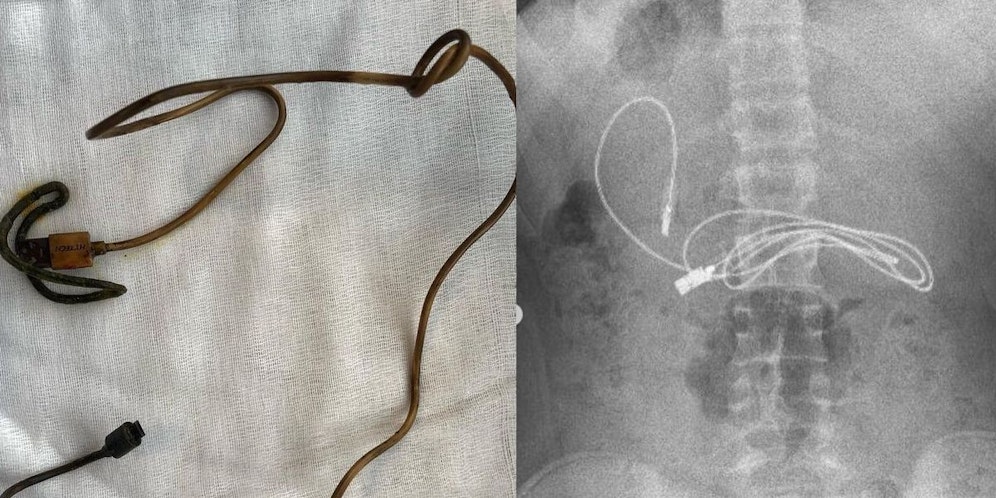

Weil ein 15-jähriger Bursche über Übelkeit und Bauchschmerzen klagte, wurde er von seiner Familie in Diyarbakir im Südosten der Türkei ins Krankenhaus gebracht. Ein Röntgenbild zeigt den Grund dafür: Ein zusammengerolltes USB-Kabel in seinem Magen.

Der Teenager wurde in einen Krankenwagen verfrachtet und in das etwa drei Stunden entfernte Firat-Universitätskrankenhaus in Elazig gebracht, wo sich ein Spezialist um die Entfernung kümmern sollte. Der Gastroenterologe, Professor Yasar Dogan, und sein Team entfernten den Fremdkörper durch eine Endoskopie (Magenspiegelung).

"Wir hatten offensichtlich Schwierigkeiten, das Kabel zu entfernen, da ein Ende des Kabels in den Dünndarm gelangt war", so Dogan. Nachdem das aufgerollte Kabel schließlich aus dem Teenager herausgezogen war, kam auch ein Haarband zum Vorschein.

Es bleibt unklar, wie oder warum er die Gegenstände geschluckt hat. "Nach erfolgreichem Abschluss des Eingriffs wurde der Patient gesund nach Hause entlassen", so Dogan weiter.